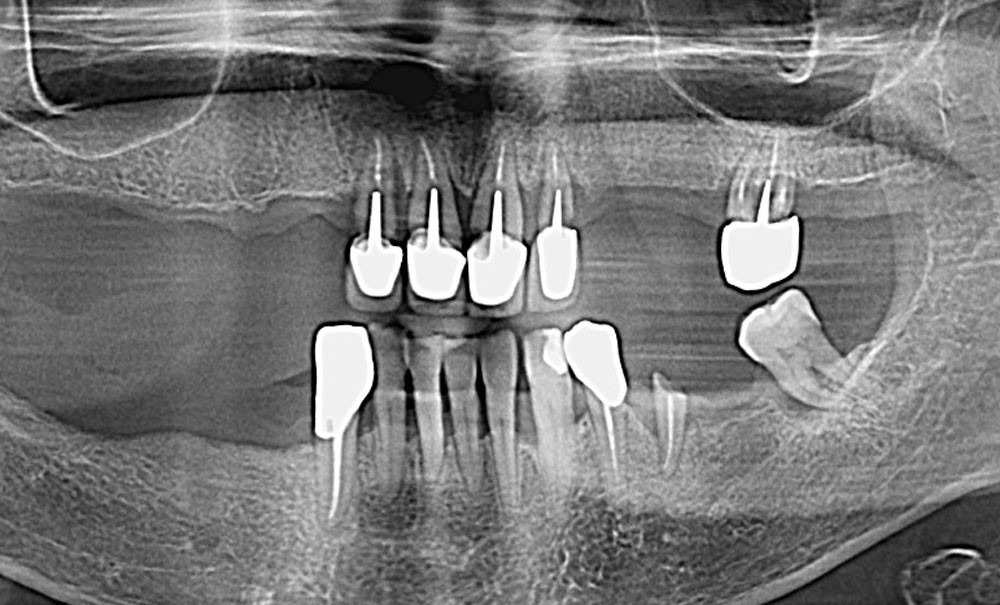

Réhabiliter une arcade complète par des implants exige une planification prothétique et chirurgicale parfois complexe ainsi qu’une retranscription clinique du projet virtuel compliquée par des erreurs d’enregistrement et/ou par l’utilisation des différents dispositifs de guidage. Les outils numériques ont gagné en maturité, mais l’écart entre validations in vitro et performances cliniques persiste en arcade complète.

La mise en charge immédiate s’appuie aujourd’hui sur deux familles de stratégies : convertir une prothèse provisoire préparée en amont ou enregistrer, de façon per ou post-opératoire, les positions implantaires pour concevoir le provisoire. Chacune offre des atouts, mais impose aussi des contraintes organisationnelles et métrologiques, surtout en contexte édenté complet.

Dans ce cadre, l’objectif de cet article est de présenter un protocole numérique hybride appelé GuideX, d’en préciser la logique et le déroulé clinique, puis d’en discuter la place par rapport aux scanners intra-oraux et à la photogrammétrie selon des critères de précision, de reproductibilité et de coût/usage. Ce protocole hybride GuideX simplifie l’acte chirurgical tout en garantissant une fidélité élevée de l’empreinte des positions implantaires et du projet prothétique provisoire.